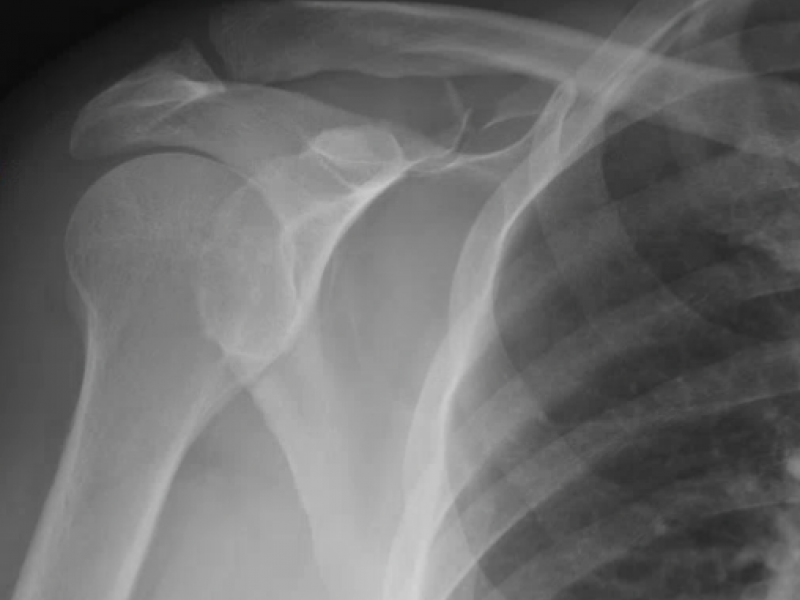

A 43 yo intoxicated male presents after he was struck by a